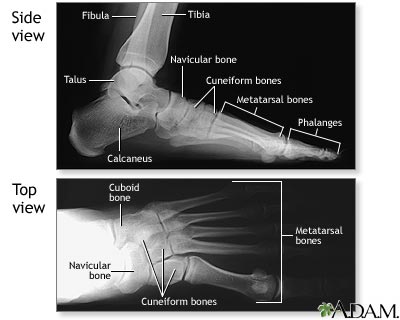

Normal foot X-ray

Along with questions of your medical history, your doctor may need to take x-rays of your foot to help aid in making a diagnosis to determine the cause of your foot pain. If the foot is broken it will be put into a cast. Toes that are broken are taped.